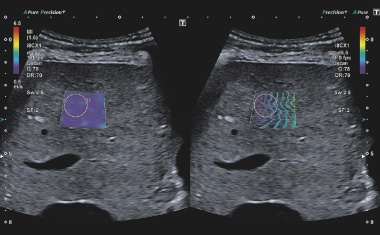

Brustultraschall kann Leben retten

Brustkrebs ist die häufigste Krebserkrankung bei Frauen: Pro Jahr erkranken in Deutschland über 70.000 neu. Umso wichtiger sind präzise, verlässliche und schonende Diagnoseverfahren – sowohl zur Erstabklärung als auch für die langfristige Nachsorge.